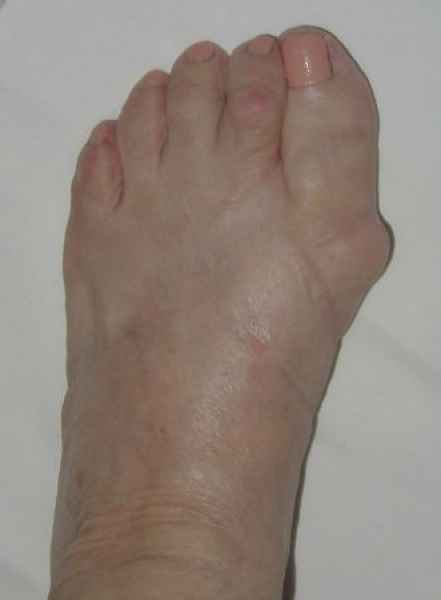

La marcha no solo es característica de la especie humana sino también de cada persona, y más aún varía según el estado de ánimo del momento. Una patología en los pies, se traduce en el rostro, en el ánimo, en el psiquismo. No sólo el dolor produce estos efectos, también un pie deformado o poco estético. En nuestra sociedad, la estética constituye un valor muy apreciado y estas alteraciones causan vergüenza fundamentalmente en las mujeres, que esconden en la playa sus pies en la arena y no pueden usar calzados elegantes.